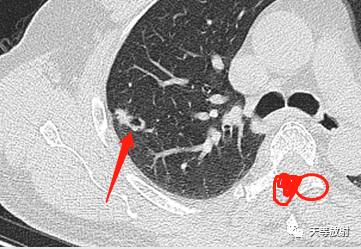

囊腔周围见长条索状影,代表组织受到牵拉聚拢。此时病例的影像学特点:

病变发生于右肺上叶;

实性结节+囊腔

实性略呈分叶状,周围见长条索状影;局部收缩,胸膜凹陷;

囊腔壁厚薄不一。这个结节表现出一定的恶性征象:分叶状实性结节,胸膜凹陷及血管聚拢改变。